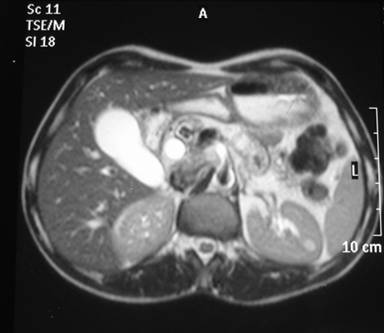

A 39-year-old male presented with upper abdominal pain and obstructive jaundice of three months and one month duration, respectively. At admission, he had cholangitis, which was treated with antibiotics. His bilirubin was 24.6 mg/dL, alkaline phosphatase 836 IU/L, SGOT 96 IU/L (reference range: 0-40 IU/L) and SGPT 55 IU/L (reference range: 0-35 IU/L). Two attempts at biliary stenting failed due to failure to cannulate the common bile duct. MRI of the abdomen with MRCP showed a dilated main pancreatic duct (1.6 cm) with multiple signal voids suggestive of calculi and a type I choledochal cyst (Figures 1 and 2). An abnormal pancreaticobiliary duct junction was not present. There was no evidence of a stricture at the lower end of the common bile duct and a 10F feeding tube could easily be passed through. He underwent a Frey’s procedure along with excision of the choledochal cyst. There were no postoperative complications and the patient was discharged on postoperative day 7. At a 6-month follow-up, he developed abdominal pain associated with vomiting. A barium study showed a stricture at the second part of the duodenum. Endoscopy confirmed the stricture with overlying normal mucosa. As the patient could not tolerate liquids, he underwent a gastrojejunostomy. The postoperative period was uneventful. At a 6-week follow-up, he was doing well.

Figure 2. MRI T2 weighted image showing a dilated common bile duct in the intrapancreatic portion with calculi in the pancreatic duct. |